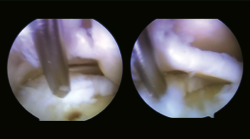

Figura 4. Acceso artroscópico a través de la sindesmosis a la lesión osteocondral. Nanoperforaciones. Se observa lesión condral inestable con lengüeta de base medial.

En un segundo tiempo se realizó un portal de trabajo mediante acceso transindesmótico anterior a 4 cm desde la línea tibioastragalina (Figura 3), previa disección roma en la piel, valorando la accesibilidad desde este punto de entrada a la lesión osteocondral previamente con una aguja de venopunción de 21 G × 1 1/2” (0,8 × 40 mm) y una vez localizado el punto de entrada con aguja de Kirschner de 1,5 mm de diámetro. Posteriormente, se realizaron nanoperforaciones en el hueso subcondral (Figura 4), reinserción del cartílago con implante reabsorbible de copolímero poliláctico (SmartNail®, ConMed Linvatec, Largo, FL) (Figura 5).